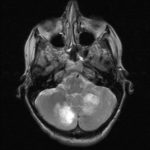

Cette masse peut entrainer notamment :

- Une irritation du cerveau qui se manifeste par une épilepsie

- Une compression voire destruction d’une partie du cerveau causant un affaiblissement ou une perte d’une fonction du cerveau

- Une augmentation de la pression à l’intérieur du crâne (espace inextensible à l’intérieur duquel vient s’ajouter le volume de la tumeur), ce qui va se manifester initialement par des maux de tête d’aggravation progressive qui vont s’associer à des nausées, des vomissements, des troubles visuels… Cet état peut aboutir à la perte de la vue dans les formes d’évolution lente et au décès dans les formes d’évolution rapide.